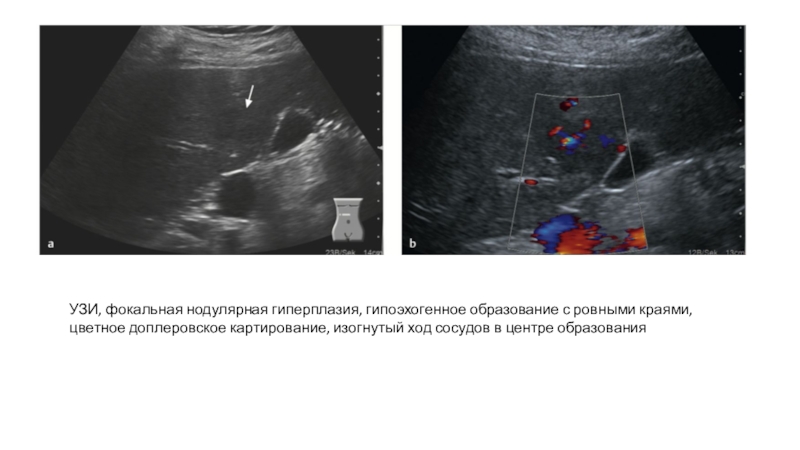

Слайд 22УЗИ, фокальная нодулярная гиперплазия, гипоэхогенное образование с ровными краями, цветное

доплеровское картирование, изогнутый ход сосудов в центре образования

УЗИ, фокальная нодулярная гиперплазия, гипоэхогенное образование с ровными краями, цветное доплеровское картирование, изогнутый ход сосудов в центре